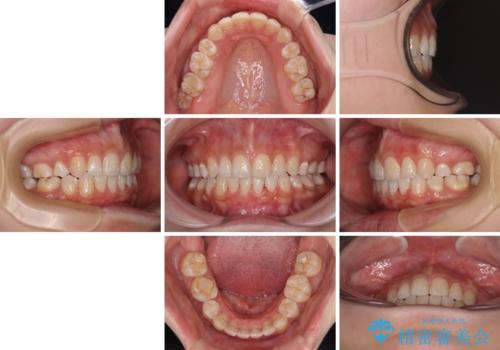

前に出ている上顎 抜歯矯正で唇を閉じやすく

第二小臼歯抜歯はイレギュラーな治療手段であり、治療期間が延びる傾向にありますが、舌のトレーニングをしっかりと行ってくださり、2年弱という非常に短い期間で理想的な仕上がりを達成することができました。